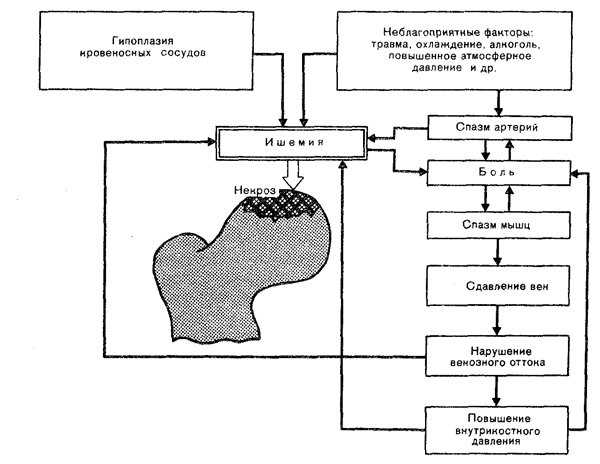

- травматическая теория – нарушение кровообращения происходит из-за травмы;

- сосудистая теория – маленькие сосуды перекрываются бляшками, вызывают ишемию и лишают ткани доступа к крови.

При обоих вариантах происходит нарушение костного питания, которое может быть при следующих условиях: